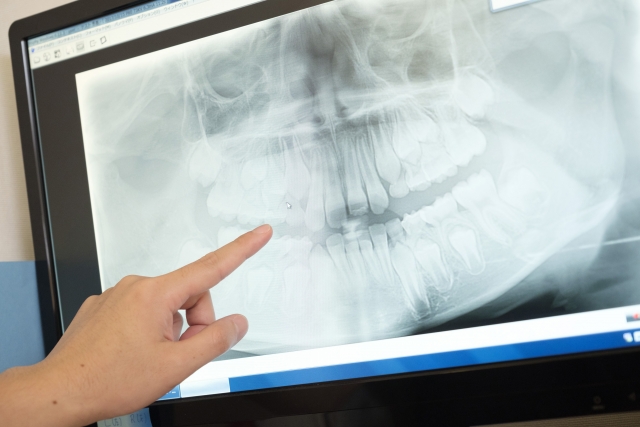

子どもにインプラントはできない?

- 予防

子どもにもインプラント治療は可能...

- 歯科治療の安全性